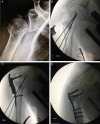

Fig. 3

(A) Anteroposterior radiograph of the right shoulder showing valgus impacted fracture of the proximal humerus. (B) Intraoperative fluoroscopy showing fracture reduction, synthetic graft and provisional fixation with metal wires. (C) Fixation using locked plate. (D) Final osteosynthesis.